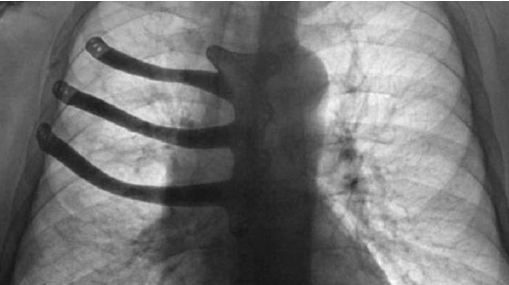

وكالات - الاقتصادي - تمكن أطباء موريسون بمدينة سوانسي البريطانية من طبع الجزء المستأصل من القفص الصدري لمريض عمره 71 سنة باستخدام طابعة ثلاثية الأبعاد.

اضطر الأطباء إلى استئصال نصف عظم القص وثلاثة أضلاع من القفص الصدري للمريض بيتر ماغزو البالغ من العمر 71 سنة بسبب ورم سرطاني. بحسب ABMU Health Board.

يعد الجراحون عادة في مثل هذه الحالات الأجزاء المستأصلة من الإسمنت الطبي أثناء العملية. بيد أن الطابعة ثلاثية الأبعاد سمحت لهم الآن بطبع الأجزاء المستأصلة من سبيكة تيتانيوم وتقليص فترة العملية ساعتين. وأثناء طبع هذه الأجزاء استخدم التصوير المقطعي للقفص الصدري للمريض. وهذه هي أول عملية طبع مثل هذه الأجزاء في بريطانيا.